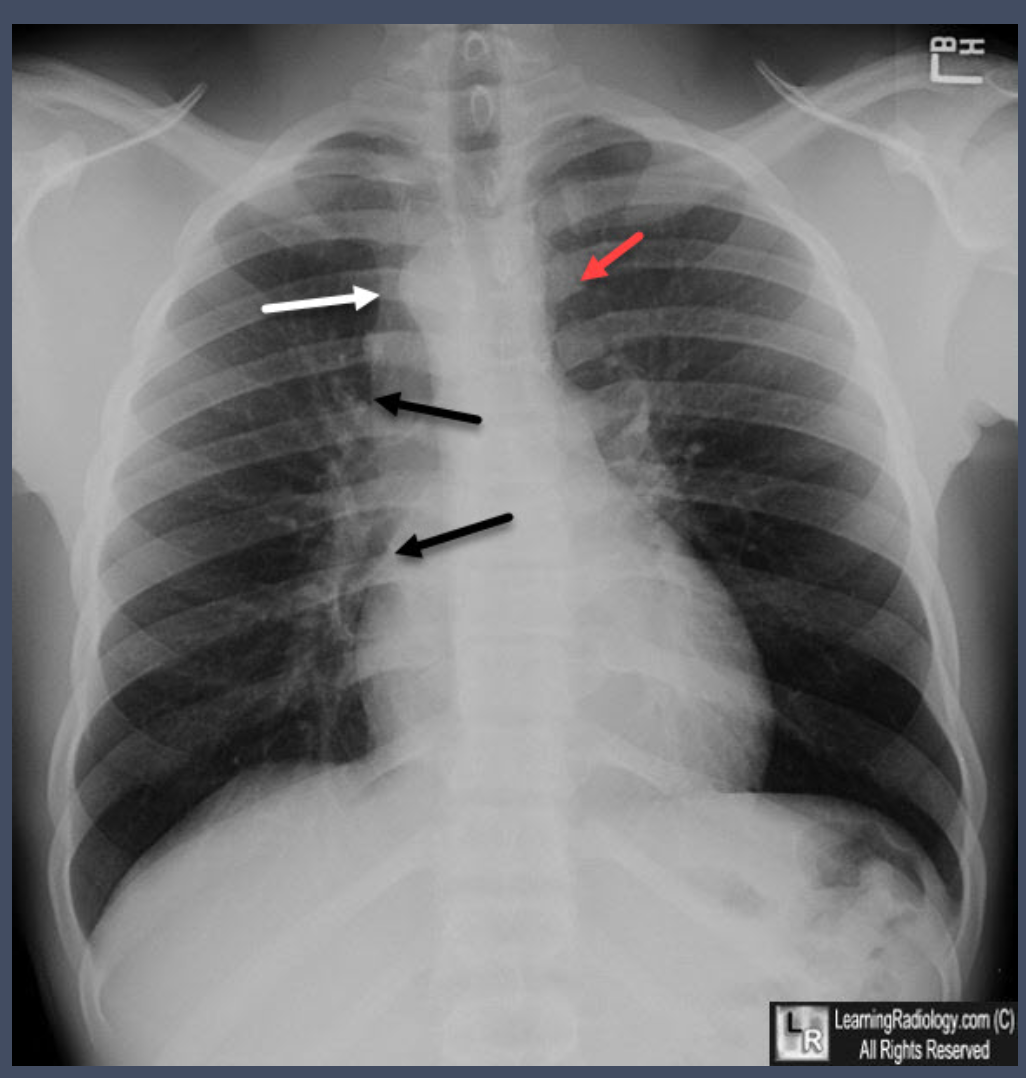

what is the dx?

what sign is demonstrated

Chen sign is described as the prominence of left basal pulmonary vasculature compared to the right base due to the asymmetric increase in pulmonary blood flow to the left lung. It is secondary to preferential blood flow into the left pulmonary artery after passing through the stenosed pulmonary valve during systole.

Enlargement of the left pulmonary artery is secondary to the same effect, causing post stenotic dilatation.